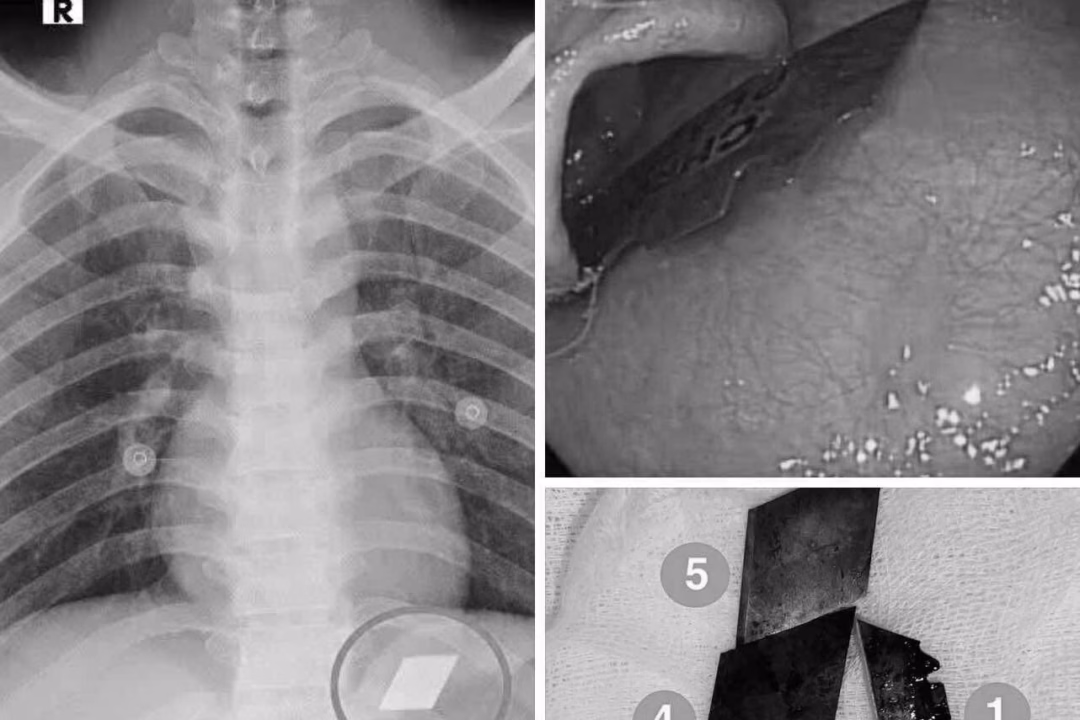

Ngày 10/7, Khoa Hồi sức cấp cứu – Bệnh viện Đa khoa Bình Dương tiếp nhận một trường hợp cấp cứu hiếm gặp. Nam bệnh nhân P.V.L, 26 tuổi, nhập viện trong tình trạng nuốt nhiều dị vật kim loại sắc nhọn, bao gồm dao rọc giấy và dao lam. Các bác sĩ đã nhanh chóng thăm khám và thực hiện chụp X-quang để xác định vị trí của các dị vật.

Qua thăm khám và chụp X-quang, các bác sĩ phát hiện các dị vật cản quang tại vị trí dạ dày. Bệnh nhân ngay lập tức được chỉ định nội soi cấp cứu để gắp bỏ dị vật. Quá trình nội soi được thực hiện dưới sự phối hợp chặt chẽ giữa ê-kíp nội soi và gây mê, đảm bảo an toàn cho bệnh nhân.

Sau một thời gian nội soi, các bác sĩ đã thành công gắp 4 lưỡi dao rọc giấy ra khỏi dạ dày và một phần lưỡi dao lam mắc tại vùng hạ họng – miệng thực quản. Thủ thuật được thực hiện thành công và bệnh nhân được theo dõi sát tình trạng sức khỏe sau đó.